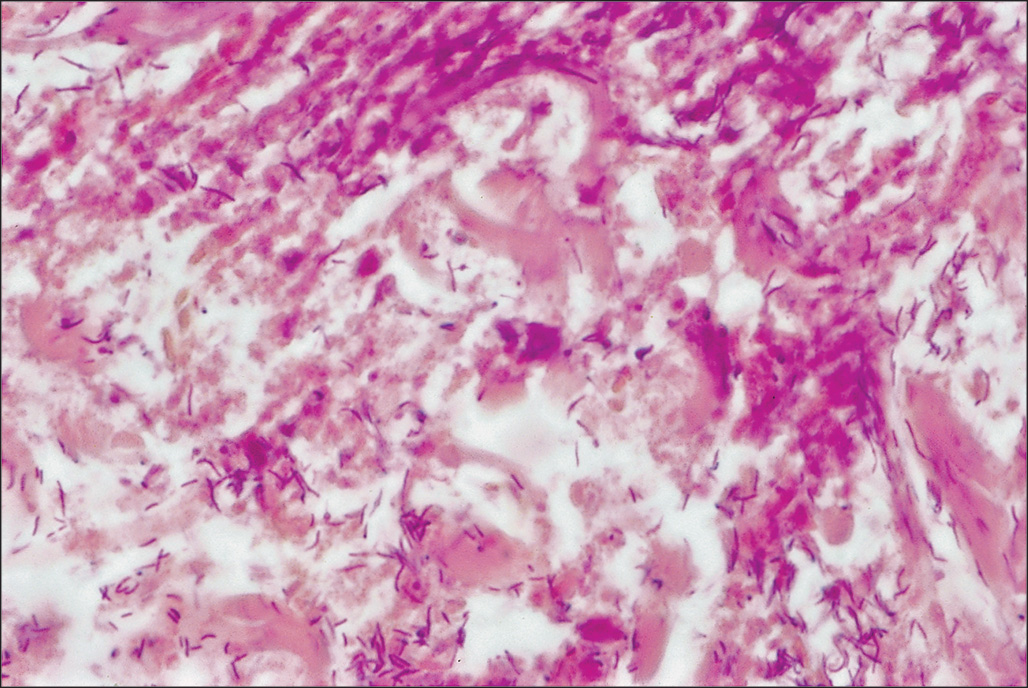

Invasive wound infections manifest clinically with wound color changes, exudate, and odor. Within a short time, partial-thickness burns progress to full-thickness necrosis and begin expanding into unburned tissues. The 2007 ABA Consensus Conference defined invasive infections as follows: “the presence of pathogens in a burn wound at concentrations sufficient in conjunction with depth, surface area involved, and age of patient, to cause suppurative separation of eschar or graft loss, invasion of adjacent unburned tissue or cause the systemic response of sepsis syndrome.” Goal-standard diagnosis is made with histologic examination; however, clinical exam and quantitative cultures usually suffice ( Fig. 10.6 ). It should be noted that sepsis does not always develop during invasive infections ( Fig. 10.7 ). Treatment must be immediate and include aggressive surgical intervention augmented by the administration of systemic and topical antimicrobials. If no culture results are initially available, then a broad-spectrum empirical therapy against fungi and drug-resistant gram-positive and-negative organisms should be initiated until culture data become available. As discussed earlier, these definitions have been demonstrated to be somewhat inadequate in multiple series, but a standard replacement has not yet gained broad acceptance. Surgical extirpation must be aggressive and encompass excision of all necrotic and infected tissue, including fascia and muscle when warranted. Definitive wound coverage is not always indicated in this extirpative operation as dressing changes and hydrotherapy may be needed to further decrease heavy bacterial loads. In cases where tissue has already been excised or there is a life-threatening infection, limb amputation may be indicated. Topical antimicrobials and assiduous washing technique are indicated after extirpation to suppress microbial growth; however, the optimal methodology is to prevent infection, with swift action being taken should an infection arise.

Gram-negative bacilli invading deep viable tissue. Histopathologic confirmation is the gold standard test to diagnose burn wound infection by bacteria in viable tissue. Shown is a typical hematoxylin and eosin–stained section at 1000× magnification.